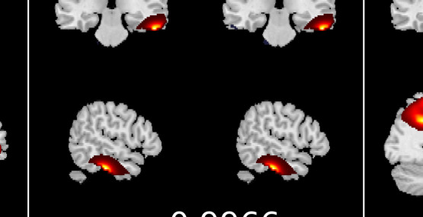

In the last two decades, unsupervised latent variable models---blind source separation (BSS) especially---have enjoyed a strong reputation for the interpretable features they produce. Seldom do these models combine the rich diversity of information available in multiple datasets. Multidatasets, on the other hand, yield joint solutions otherwise unavailable in isolation, with a potential for pivotal insights into complex systems. To take advantage of the complex multidimensional subspace structures that capture underlying modes of shared and unique variability across and within datasets, we present a direct, principled approach to multidataset combination. We design a new method called multidataset independent subspace analysis (MISA) that leverages joint information from multiple heterogeneous datasets in a flexible and synergistic fashion. Methodological innovations exploiting the Kotz distribution for subspace modeling in conjunction with a novel combinatorial optimization for evasion of local minima enable MISA to produce a robust generalization of independent component analysis (ICA), independent vector analysis (IVA), and independent subspace analysis (ISA) in a single unified model. We highlight the utility of MISA for multimodal information fusion, including sample-poor regimes and low signal-to-noise ratio scenarios, promoting novel applications in both unimodal and multimodal brain imaging data.